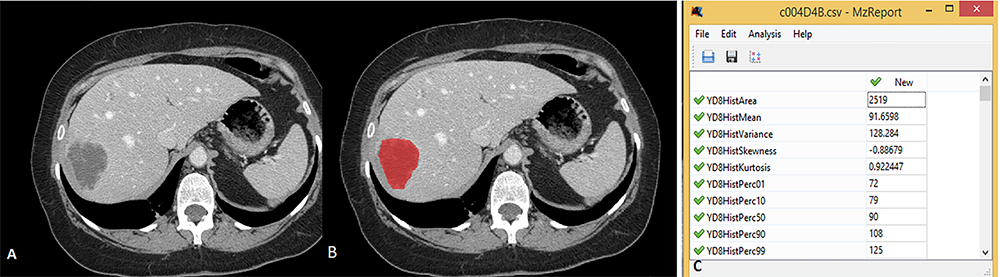

We used an anonymized dataset from a study entitled ‘Colorectal Liver Metastases (CRLM)’ registered in ‘The Cancer Imaging Archive (TCIA) database and anonymized CT images of the cases included in this study.10 We obtained pretreatment CT images of 197 cases originally enrolled in the study. Image analysis and statistical evaluation were carried out between January and March 2024. All data acquisition and utilization adhered to TCIA data use guidelines.11 The collected CT images were then reviewed using the ‘Radiant DICOM Viewer 2020.2.3’ software. After evaluation, 197 patients who underwent contrast-enhanced abdominal CT examination with a slice thickness of 1.3 mm were included in our study. In the contrast-enhanced abdominal CT examinations constituting the study group, 120 mL contrast material was administered intravenously at a rate of 3 mL/sec, and the delay time was set as 90 s. For image analysis, a single observer, M.D., with 10 years of experience in radiology, evaluated the CT images of each case using the same window settings (window level 20 and window width 380). The axial image showing the tumor at maximum size was identified and registered. The saved images were then opened using ‘qMaZda v4.6’ software (MaZda for Windows, B11 ver. 4.6, www.eletel.p.lodz.pl/programy/mazda/).12 Tumor boundaries, including necrotic and cystic regions, were manually drawn. Histogram parameters such as mean, variance, skewness, kurtosis, 1st percentile (P), 10th P, 50th P, 90th P and 99th P were calculated over the determined areas and evaluated for each case individually (Figure 1).

Figure 1. 65-year-old male patient with Colorectal Liver metastasis.. (A) Contrast-enhanced abdominal CT images show a metastatic lesion in the right lobe of the liver. (B) Two-dimensional segmentation of metastasis (red) from the same level using qMazda V.6 software. (C) Quantitative values of the histogram parameters of the area determined in image B